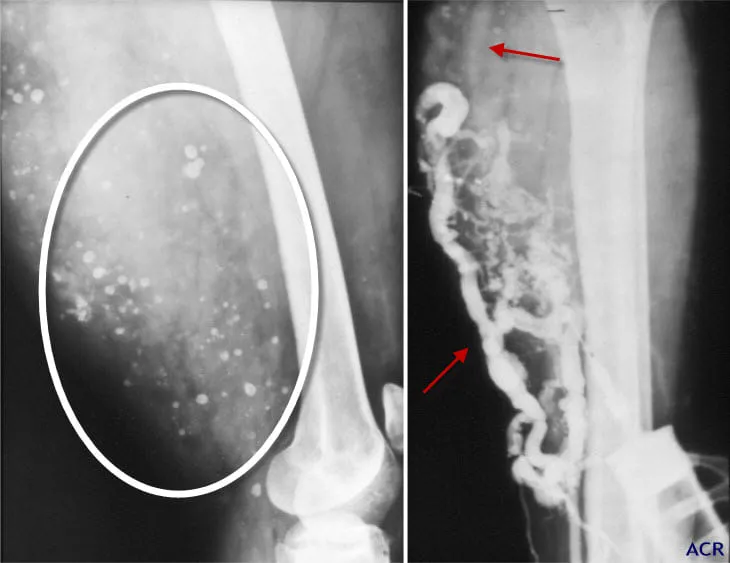

蘇一峰認為是典型的血管瘤,認為應該沒有造假可能。劉彥澧提供

而劉彥澧公布個人病歷,2009年與上週的核磁共振造影都清楚顯示,小腿血管瘤至今還在,大小為長13.4公分、寬9.1公分及厚度2.7公分,醫生也說無法以外科手術摘除,否則會走路困難。

名醫蘇一峰也在粉專上討論此事,肌肉內血管瘤、骨骼肌血管瘤是一種罕見的良性腫瘤,慢性疼痛且運動加劇和摸得到的腫塊是最常見的症狀。最常出現在四肢尤其是下肢如大腿和小腿,在極少數情況下,它們分流血流並導致心臟衰竭。他也從影像上表示,看起來很典型,應該沒有造假的可能性,相信三總的專業判斷。